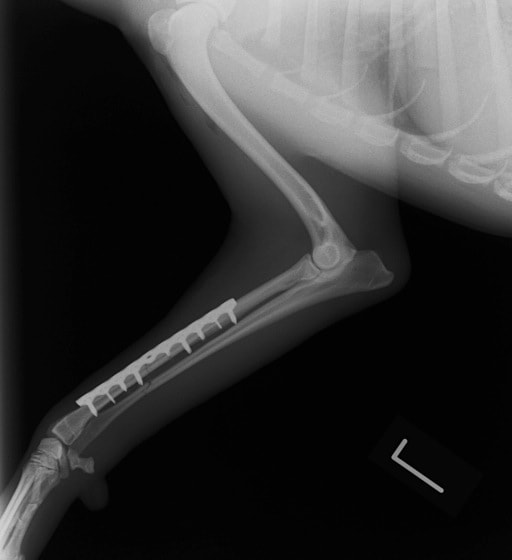

トイプードル 右遠位橈尺骨短斜骨折のALPSによる内固定

Locking Compression Plate

LCPは、スクリュー(ネジ)とプレート(金属の板)をロックする特殊な構造により骨折部位を固定する新しい世代のプレートシステムです。ひとつのホールでロッキングスクリューとスタンダードスクリューの使用を選択できるユニークな構造をしているため、骨折断端間の圧迫を目的とした従来型プレート固定法に加え、高い角度安定性を有するロッキングスクリューを用いた固定法の選択が可能です。従来のプレートシステムでは困難だった部分の骨折や癒合不全の症例に高い治療効果をもたらします。